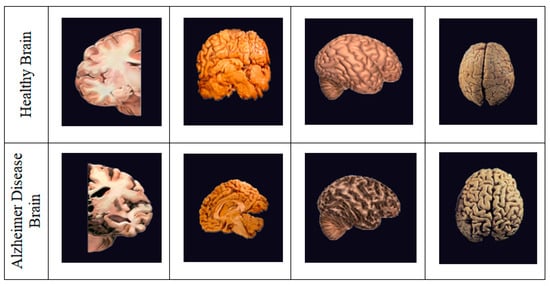

According to recent research, 1 in every 85 people might be impacted by AD by 2050 [3]. It is critical to detect and treat AD patients in their early stages. There are numerous methods available for identifying and predicting this dementia, including MRI, PET, and CT (Computed Tomography) scans, as shown in Figure 1; however, the most often used neuroimaging modality for diagnosing AD patients is MRI [4,5]. Earlier research studies have used MRI-based classification techniques with Machine and Deep Learning algorithms [6]. This paper aims to develop the finest prediction and detection methods possible with the assistance of radiologists, clinicians, and carers to save time and aid patients suffering from this condition [7,8].

Figure 1.

Healthy Brain vs. Alzheimer’s Diseased Brain. Compared to a healthy brain, the Alzheimer’s drain can be noted with shrinkage in size, less moisture, and enlarged ventricles.